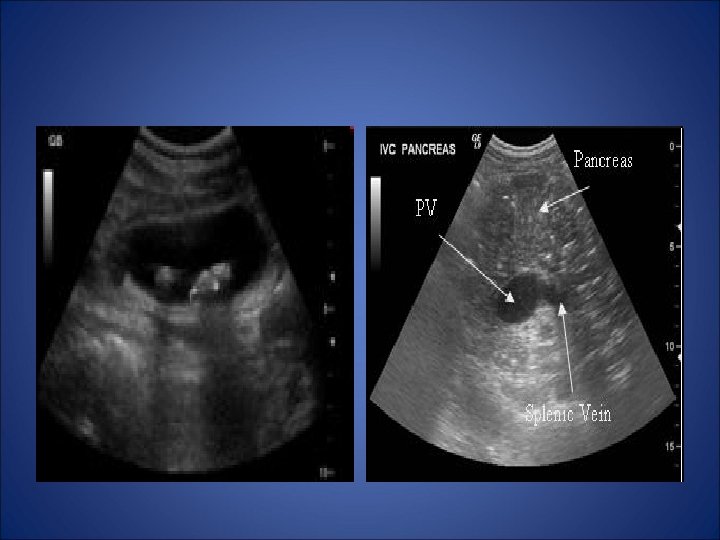

Ecografia abdominală relevă: • • • colecist cu pereţi îngroşaţi, locuit de un calcul de aproximativ 2/3 cm, pancreas mărit edemaţiat, lamă de lichid în fundul de sac Douglas.

TC abdominal